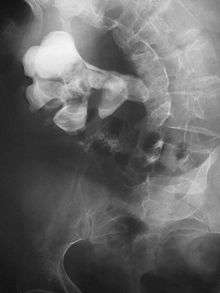

Otherwise a noncontrast helical CT scan with 5 millimeters (0.2 in) sections is the diagnostic modality of choice in the radiographic evaluation of suspected nephrolithiasis.[12][42][45][46][3] All stones are detectable on CT scans except very rare stones composed of certain drug residues in the urine,[47] such as from indinavir. Calcium-containing stones are relatively radiodense, and they can often be detected by a traditional radiograph of the abdomen that includes the kidneys, ureters, and bladder (KUB film).[47] Some 60% of all renal stones are radiopaque.[45][48] In general, calcium phosphate stones have the greatest density, followed by calcium oxalate and magnesium ammonium phosphate stones. Cystine calculi are only faintly radiodense, while uric acid stones are usually entirely radiolucent.[49]

Where a CT scan is unavailable, an intravenous pyelogram may be performed to help confirm the diagnosis of urolithiasis. This involves intravenous injection of a contrast agent followed by a KUB film. Uroliths present in the kidneys, ureters or bladder may be better defined by the use of this contrast agent. Stones can also be detected by a retrograde pyelogram, where a similar contrast agent is injected directly into the distal ostium of the ureter (where the ureter terminates as it enters the bladder).[45]